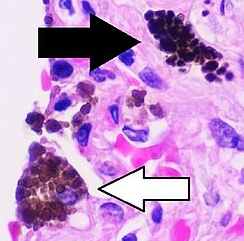

Tattoo Ink in Macrophage

In the above figure, the aggregates of black dots, which look trapped, are the ink particles captured in the macrophages (the pink part). And since ink cannot be broken down by the macrophages, it stays like that - essentially being stored by the macrophage, and making the tattoo visible.